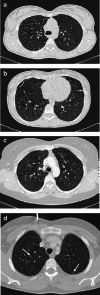

Objectives: Pulmonary Langerhans cell histiocytosis (PLCH) is a rare interstitial granulomatous disease that usually affects young adults who are smokers. Chest computed tomography (CT) allows a confident diagnosis of PLCH only in typical presentation, when nodules, cavitated nodules and cysts coexist and predominate in the upper and middle lungs.

Methods: This article includes a pictorial essay of typical and atypical presentations of PLCH at initial chest CT. Various appearances of PLCH are illustrated and possible differential diagnosis is discussed.

Results: PLCH can present with some aspecific features that may cause diagnosis of the initial disease to be overlooked or other pulmonary diseases to be suspected. In cases of nodule presentation alone, the main differential diagnosis should include lung metastasis, tuberculosis and other infections, sarcoidosis, silicosis and Wegener's disease. In cases of cysts alone, the most common diseases to be differentiated are centrilobular emphysema and lymphangiomyomatosis. Clinical symptoms are usually non-specific, although a history of cigarette smoking, coupled with the presence of typical or suggestive findings at imaging, is key to suspecting the disease. Atypical presentations require surgical biopsy for diagnosis.

Teaching points: • PLCH is a rare interstitial smoking-related disease that usually affects young adults. • The typical first CT shows a mix of nodules, cavitary nodules and cysts in the upper-middle lungs. • Atypical appearance, either cysts or nodules alone, mandates that other diagnoses be considered. • Lung cystic involvement correlates with lung function abnormalities and predicts functional decline. • Integration of the clinical history and imaging results is key to diagnosis.